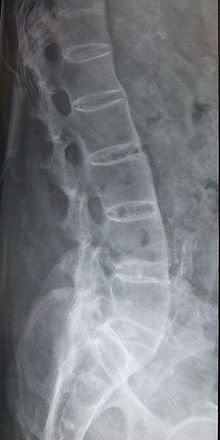

I thought that this would be helpful to those that are looking for answers or those that would like to see what radiographic evidence looks like and how it is defined... (a) T1-weighted and (b) short tau inversion recovery (STIR) magnetic resonance images of lumbar and lower thoracic spine in psoriatic arthritis. Signs of active inflammation are seen at several levels (arrows). In particular, anterior spondylitis is seen at level L1/L2 and an inflammatory Andersson lesion at the upper vertebral endplate of L3. The fourth, fifth and sixth vertebra contains certain peculiarities, which are detailed below. Radiology shows the appearance of "fluffy, new" bone or bridging/fusion.